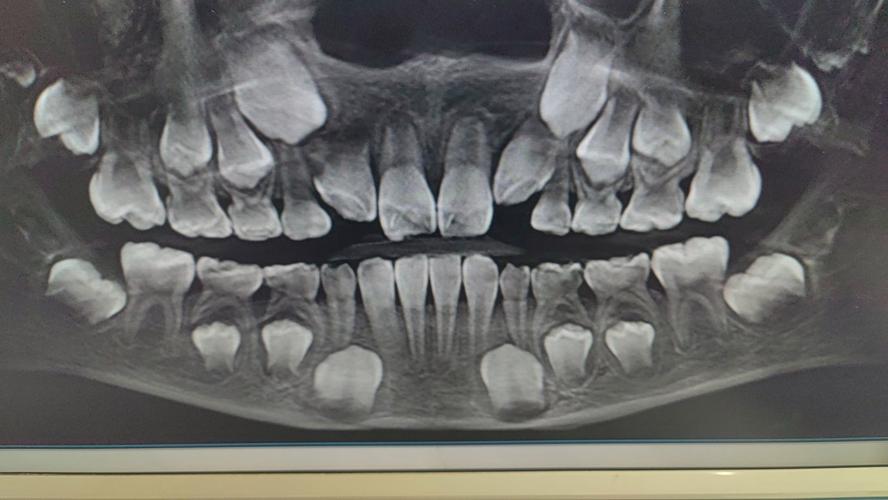

曲面断层片(全景片):全口牙齿与颌骨的“全景地图”

曲面断层片是矫正检查中最基础的影像学检查,通过一次曝光即可获取全口牙齿、牙槽骨、上下颌骨及部分颌面结构的二维图像,其主要作用包括:观察牙齿数量(是否存在多生牙、缺失牙或阻生智齿)、牙根形态(是否弯曲、短小或吸收)、牙槽骨高度与密度(评估牙周支持能力)、恒牙胚发育情况(青少年矫正中尤为重要)以及颌骨内的囊肿、肿瘤等病变。

适用情况:所有接受矫正的患者均需拍摄,作为常规筛查工具,其优势在于辐射剂量较低(约0.02mSv,相当于自然背景辐射2天)、检查速度快,能快速掌握口腔整体概况,曲面断层片的局限性在于图像为二维重叠,无法清晰显示牙根与颌骨的立体关系,复杂病例需结合其他影像进一步评估。